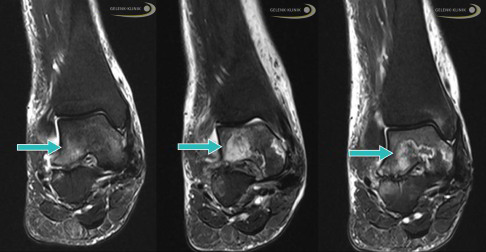

Besonders hilfreich für die Untersuchung von Knochenveränderungen sind Schnittbildverfahren, die mit Röntgenstrahlung arbeiten. Neben dem Kernspin (MRT) und SPECT ist besonders die digitale Volumentomographie (DVT) des Sprunggelenks wertvoll, um die charakteristischen Veränderungen im Innern des Sprungbeins darzustellen.

Nach einem Kollaps des Knochens unter dem Gelenkknorpel (subchondraler Knochen) kann nur das DVT (digitale Volumentomografie) die genaue Lage und Belastung der Knochenstrukturen darstellen. Das Röntgenbild als Überlagerungsbild ist ebenfalls eine gute Möglichkeit, die häufig aber – anders als die hochauflösende röntgenbasierte Schnittbilddiagnostik wie DVT oder CT – nicht die gesamte Situation der Strukturen darstellt. Daher ist ein Röntgenbild für eine Therapieentscheidung oft nicht ausreichend.